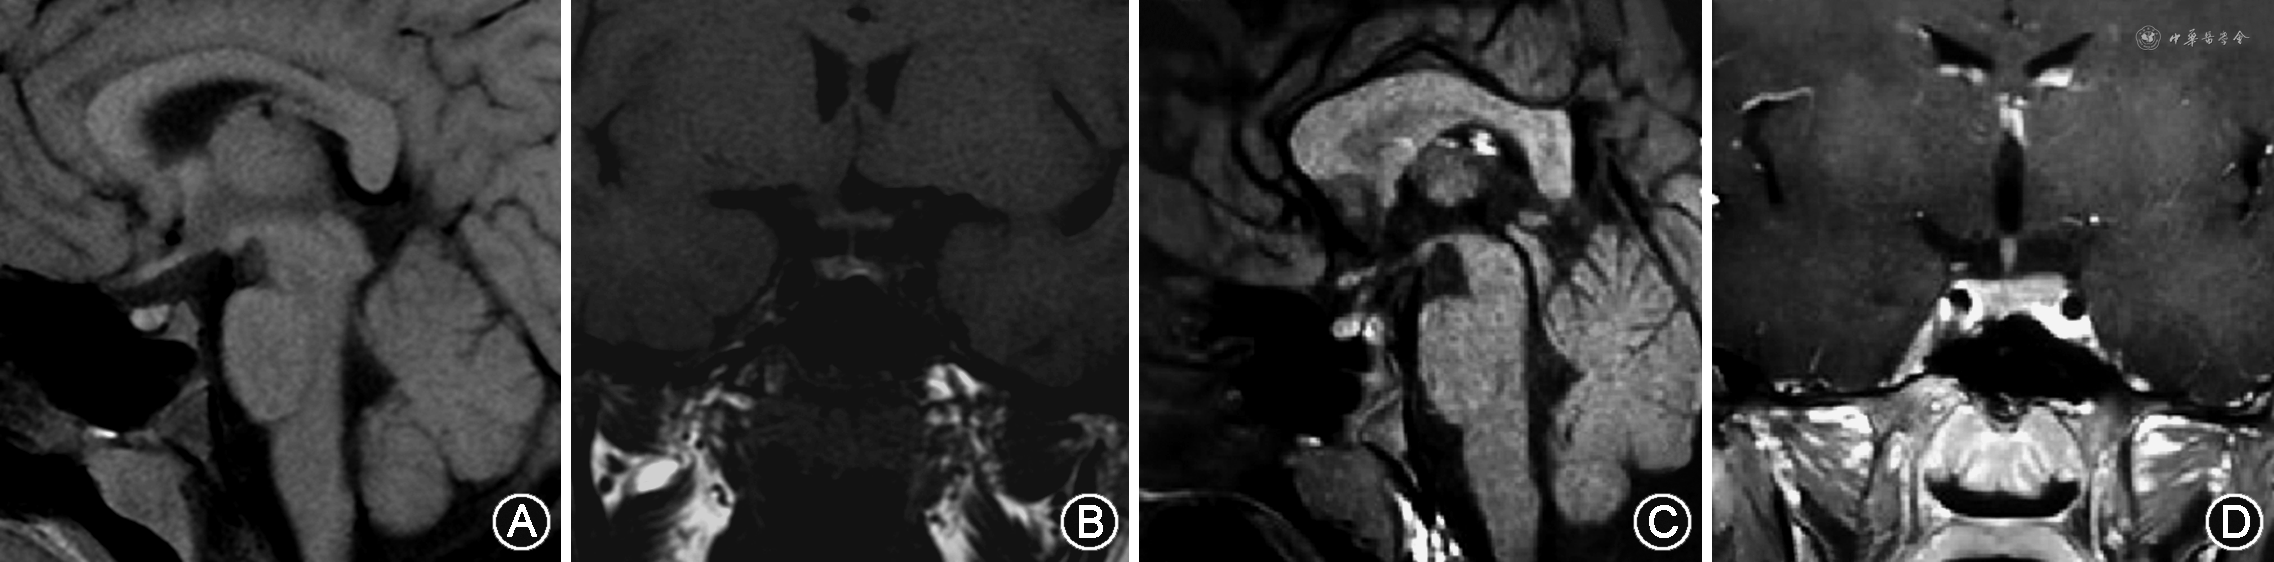

辅助检查:血生化结果:血钠:147 mmol/L,血氯:112 mmol/L,血糖、血钙正常;血常规结果:白细胞:6.10×109/L,中性粒细胞百分比:56.4%;垂体前叶功能评估提示生长激素轴、肾上腺激素轴、甲状腺激素轴功能大致正常,性腺轴符合青春期前的儿童水平(表1);禁水试验:禁水6 h后可见血渗透压升高至311 mOsm/kg、血钠升高至147 mmol/L,同时仍排出低渗尿,尿渗透压116 mOsm/kg、尿比重1.004,尿崩症定性诊断明确;简易去氨加压素试验:服用0.1 mg去氨加压素3 h后,尿量显著减少,尿渗透压升高至509 mOsm/kg,尿比重1.015,中枢性尿崩症诊断明确;尿崩症病因检查:抗核抗体谱:抗核抗体(ANA)低滴度(1∶80)阳性,核型为斑点型(S),其余自身抗体均为阴性;免疫球蛋白、补体、超敏C反应蛋白、血IgG亚类测定、甲胎蛋白、癌胚抗原、β人绒毛膜促性腺激素和血管紧张素转化酶等均正常;垂体增强MRI:鞍区、松果体、基底节区未见异常占位性病变或异常强化灶,垂体后叶短T1信号未见明显显示(图1);视野检查:无视野缺损;纯音测听及声导抗结果未见明显异常;骨龄相:骨龄5~6岁。

本例患儿幼年男童,慢性病程,自幼出现多饮、口干、多尿,饮水量多达9 L/d,尿量与饮水量相当,多尿诊断明确。多尿的病因主要包括渗透性利尿、精神性多饮及尿崩症。该患儿血糖水平正常,无甘露醇等高渗药物使用史,排除渗透性利尿可能;日、夜尿量均显著增多,夜尿5~6次/晚,且无焦虑、抑郁等精神因素,考虑精神性多饮可能性小;持续排出大量低渗尿,尿比重明显减低,考虑尿崩症可能性大。患儿禁水试验后血渗透压、血钠明显升高,同时尿渗透压、尿比重仍明显减低,尿崩症定性诊断明确;服用去氨加压素后,尿量显著减少,尿渗透压升高,表明对外源性AVP有反应,中枢性尿崩症定位诊断明确。此外,患儿垂体增强MRI提示垂体后叶短T1信号未见明确显示,表明垂体后叶缺乏储存的AVP,进一步支持中枢性尿崩症诊断。

在中枢性尿崩症病因筛查方面,肿瘤性疾病是首要常见病因。患儿无头痛、视力下降、视野缺损等颅内占位表现,垂体MRI显示未见鞍区异常占位性病变或异常强化灶,且血清肿瘤标志物未见异常,肿瘤性疾病证据不足;病程中无发热等感染表现。幼年男童非自身免疫性疾病好发人群,血清炎症指标、免疫球蛋白、补体、IgG亚类测定均正常,无感染性炎症、自身免疫性垂体炎相关证据;完善多部位超声未发现其他器官系统受累情况,考虑组织细胞病可能性小;垂体MRI显示垂体柄完整,排除垂体柄阻断综合征可能。基因检测发现患儿AVP基因出现一处错义突变,为杂合突变,其父母均不携带该突变基因,故遗传性中枢性尿崩症诊断明确。患儿母亲AVP基因为野生型,但在孕期表现出多尿症状,考虑是由于胎盘合成AVP酶,加速孕妇血液循环中的AVP降解所导致[2],产后相关症状消失也支持上述解释。